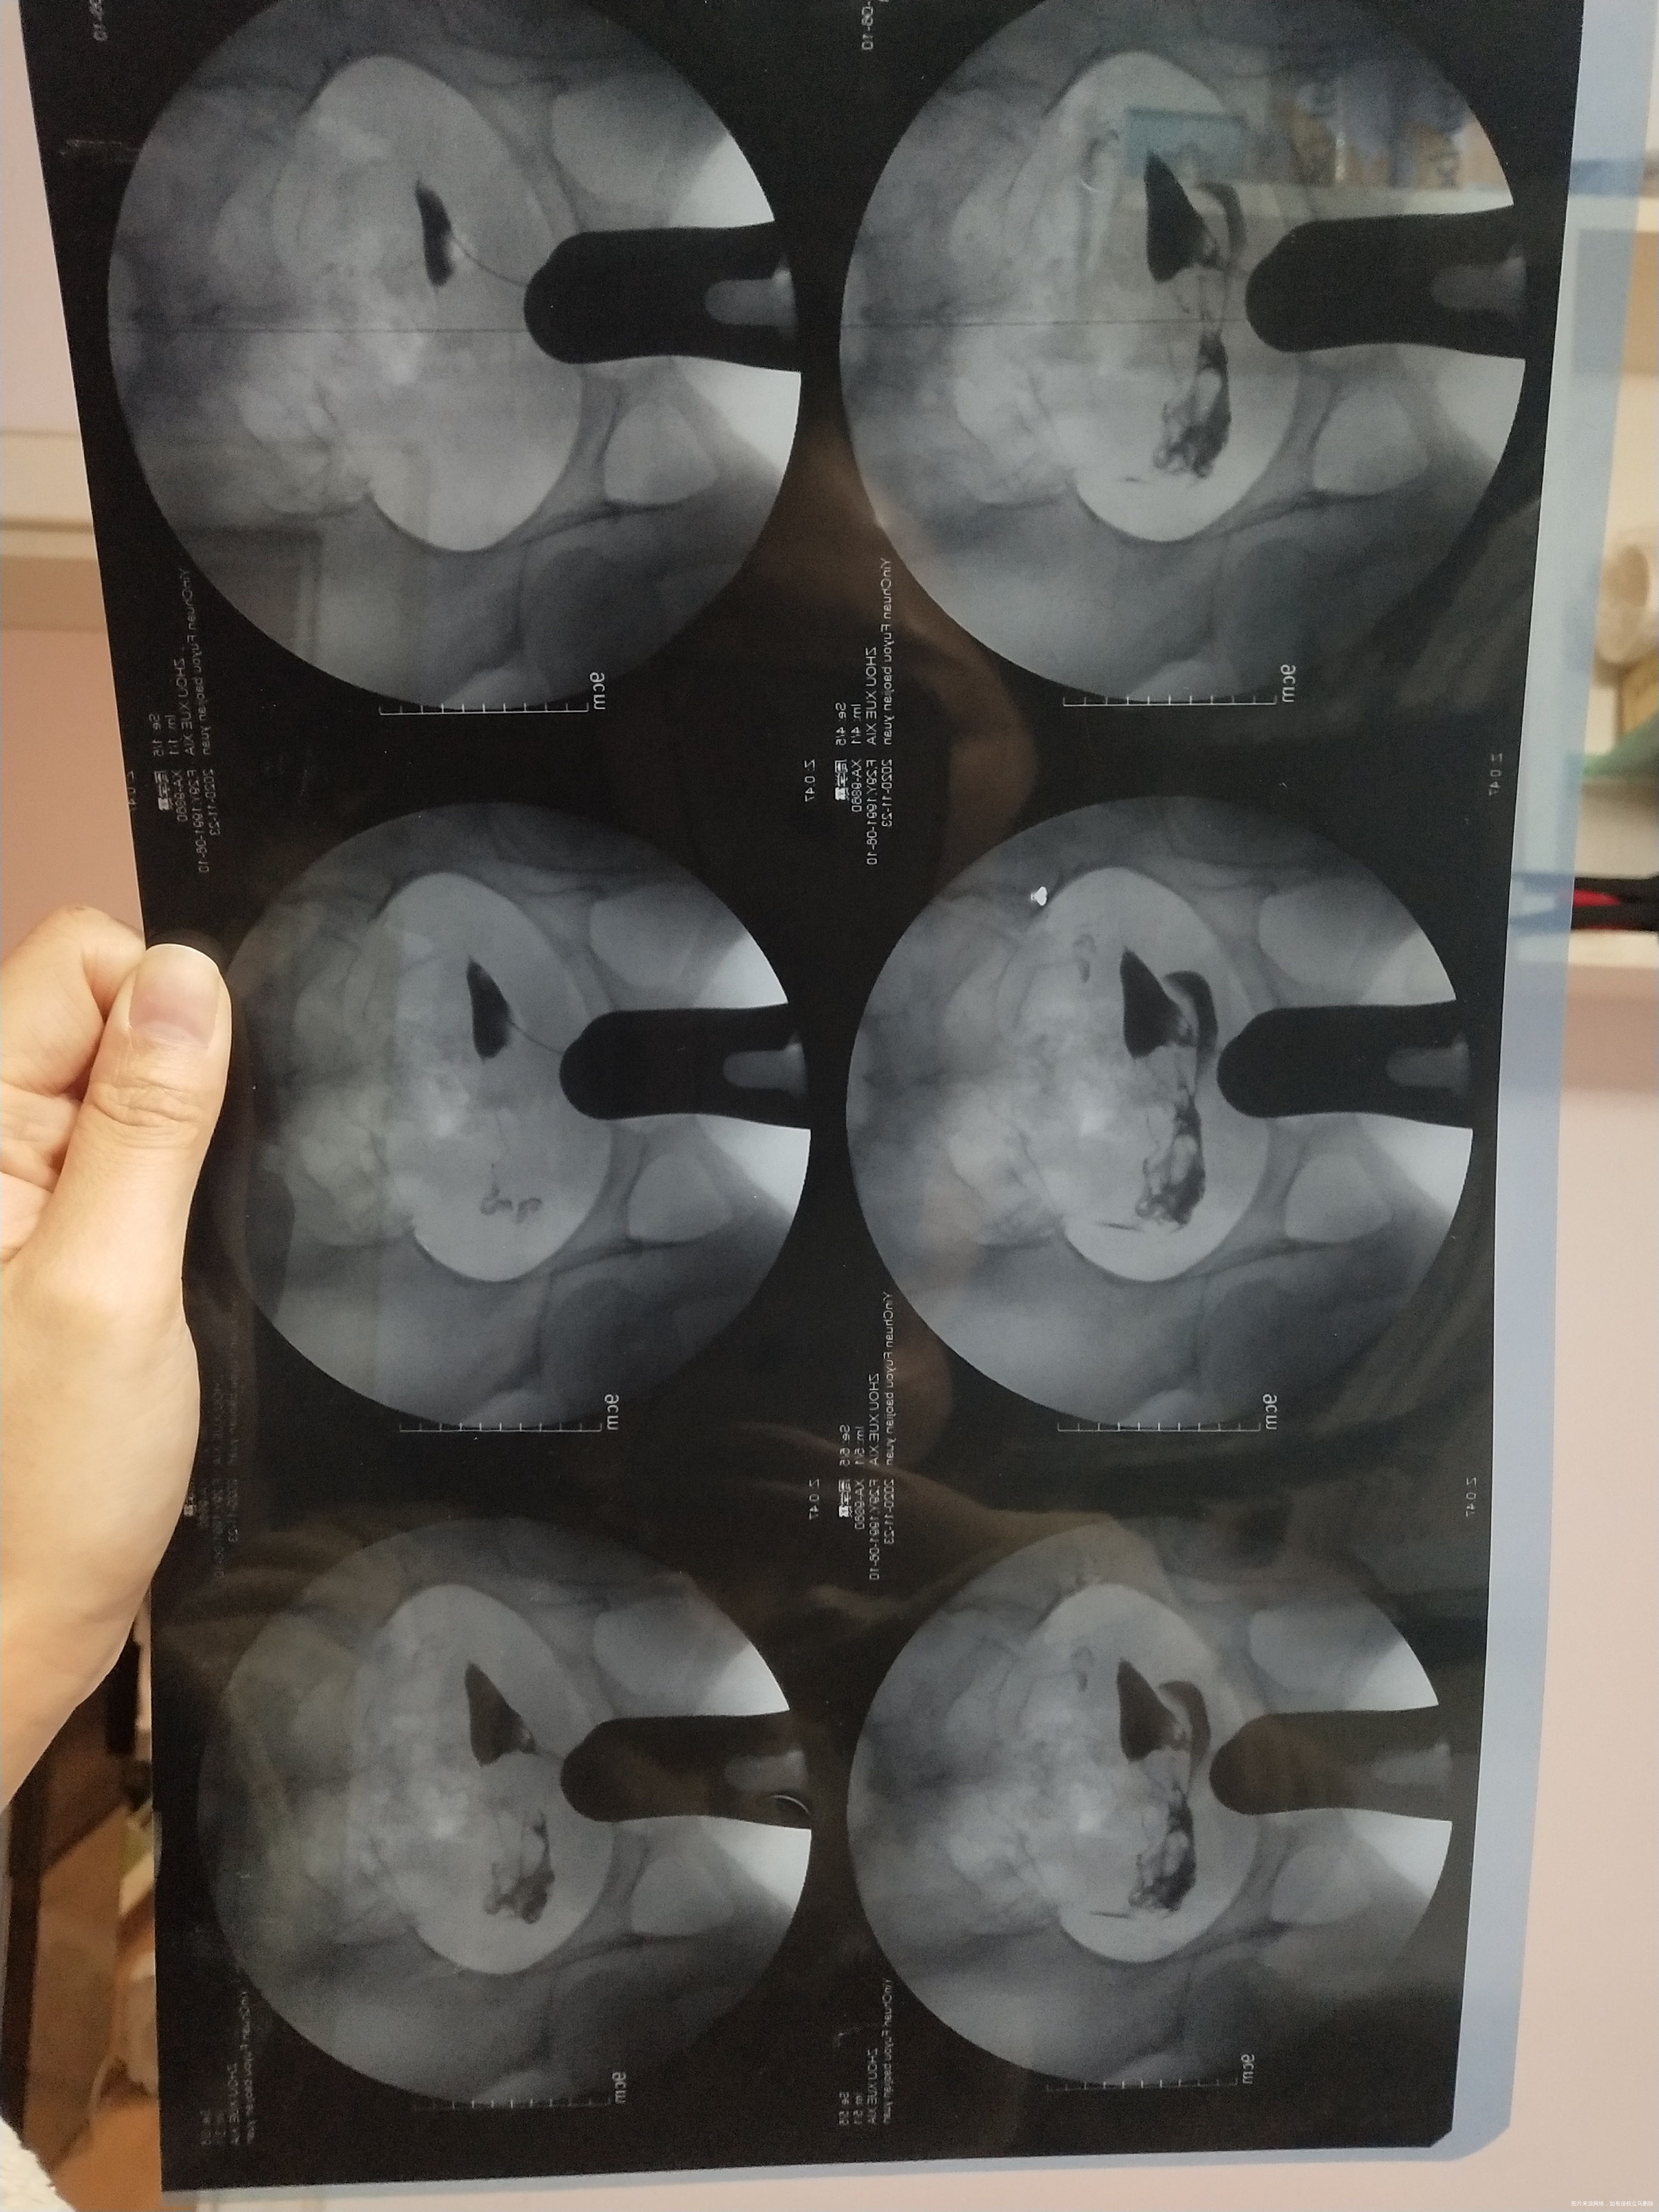

备孕两年,之前检测卵泡不破裂,有过5年的慢性阑尾炎,做了手术2年了,输卵管造影右侧不通,您看一下是做手术比较好还是先试着用左侧输卵管的去怀呢

您好,建议先用左侧去试,因为阑尾炎病史较长,右侧手术的话输卵管功能估计也不能完全恢复。男方精液检查一下,如果没有问题,也可以考虑人工授精3-6周期试试

回复 陈淑萍:那大夫左边这个是完全通畅吗?

陈淑萍 回复 :不好意思,这个图我这样不能直接判断,不清楚,拿给你的主治医生瞧瞧